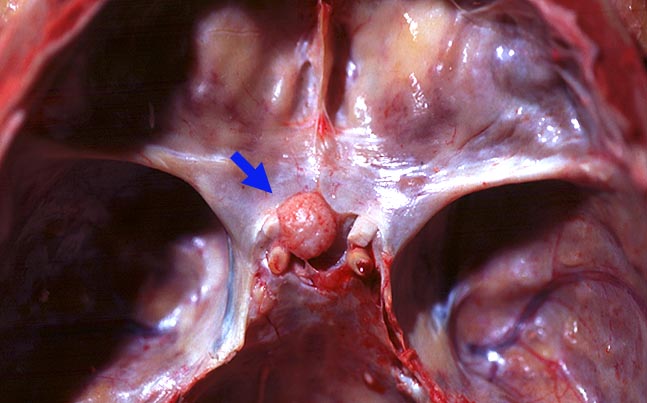

Meningeome können in Abhängigkeit von ihrer Lage vielfältige Symptome verursachen. Lokalisierte oder unspezifische Kopfschmerzen sind häufig. Die Kompression des Hirns kann epileptische Anfälle, fokale Schwäche, Dysphasie, Apathie und Somnolenz auslösen. Meningeome der Schädelbasis können eine Gefässkompression mit konsekutiver Ischämie verursachen. Intraventrikuläre Meningeome können einen obstruktiven Hydrocephalus verursachen. Meningeome in der Nähe der Sella turcica können zu einer Unterfunktion der Hypophyse führen. Typische Symptomenkomplexe sind im Literaturlink tabellarisch dargestellt. Papillenödem, Hirnnervenausfälle, Pyramidenbahnzeichen oder ein Brown Sequard Syndrom durch einseitige Kompression des Rückenmarks stellen mögliche Untersuchungsbefunde dar.

Der Dura breitbasig aufsitzender scharf begrenzter halbkugeliger Tumor.